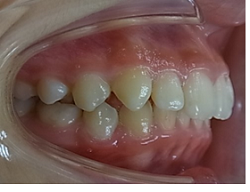

当矯正歯科医院ではMEAW法(マルチループ)で治療する事で非抜歯で治療しています。

MEAW法(マルチループ)を利用することで以下の様に上顎前突が改善されていきます。

初診時

治療途中

終了時